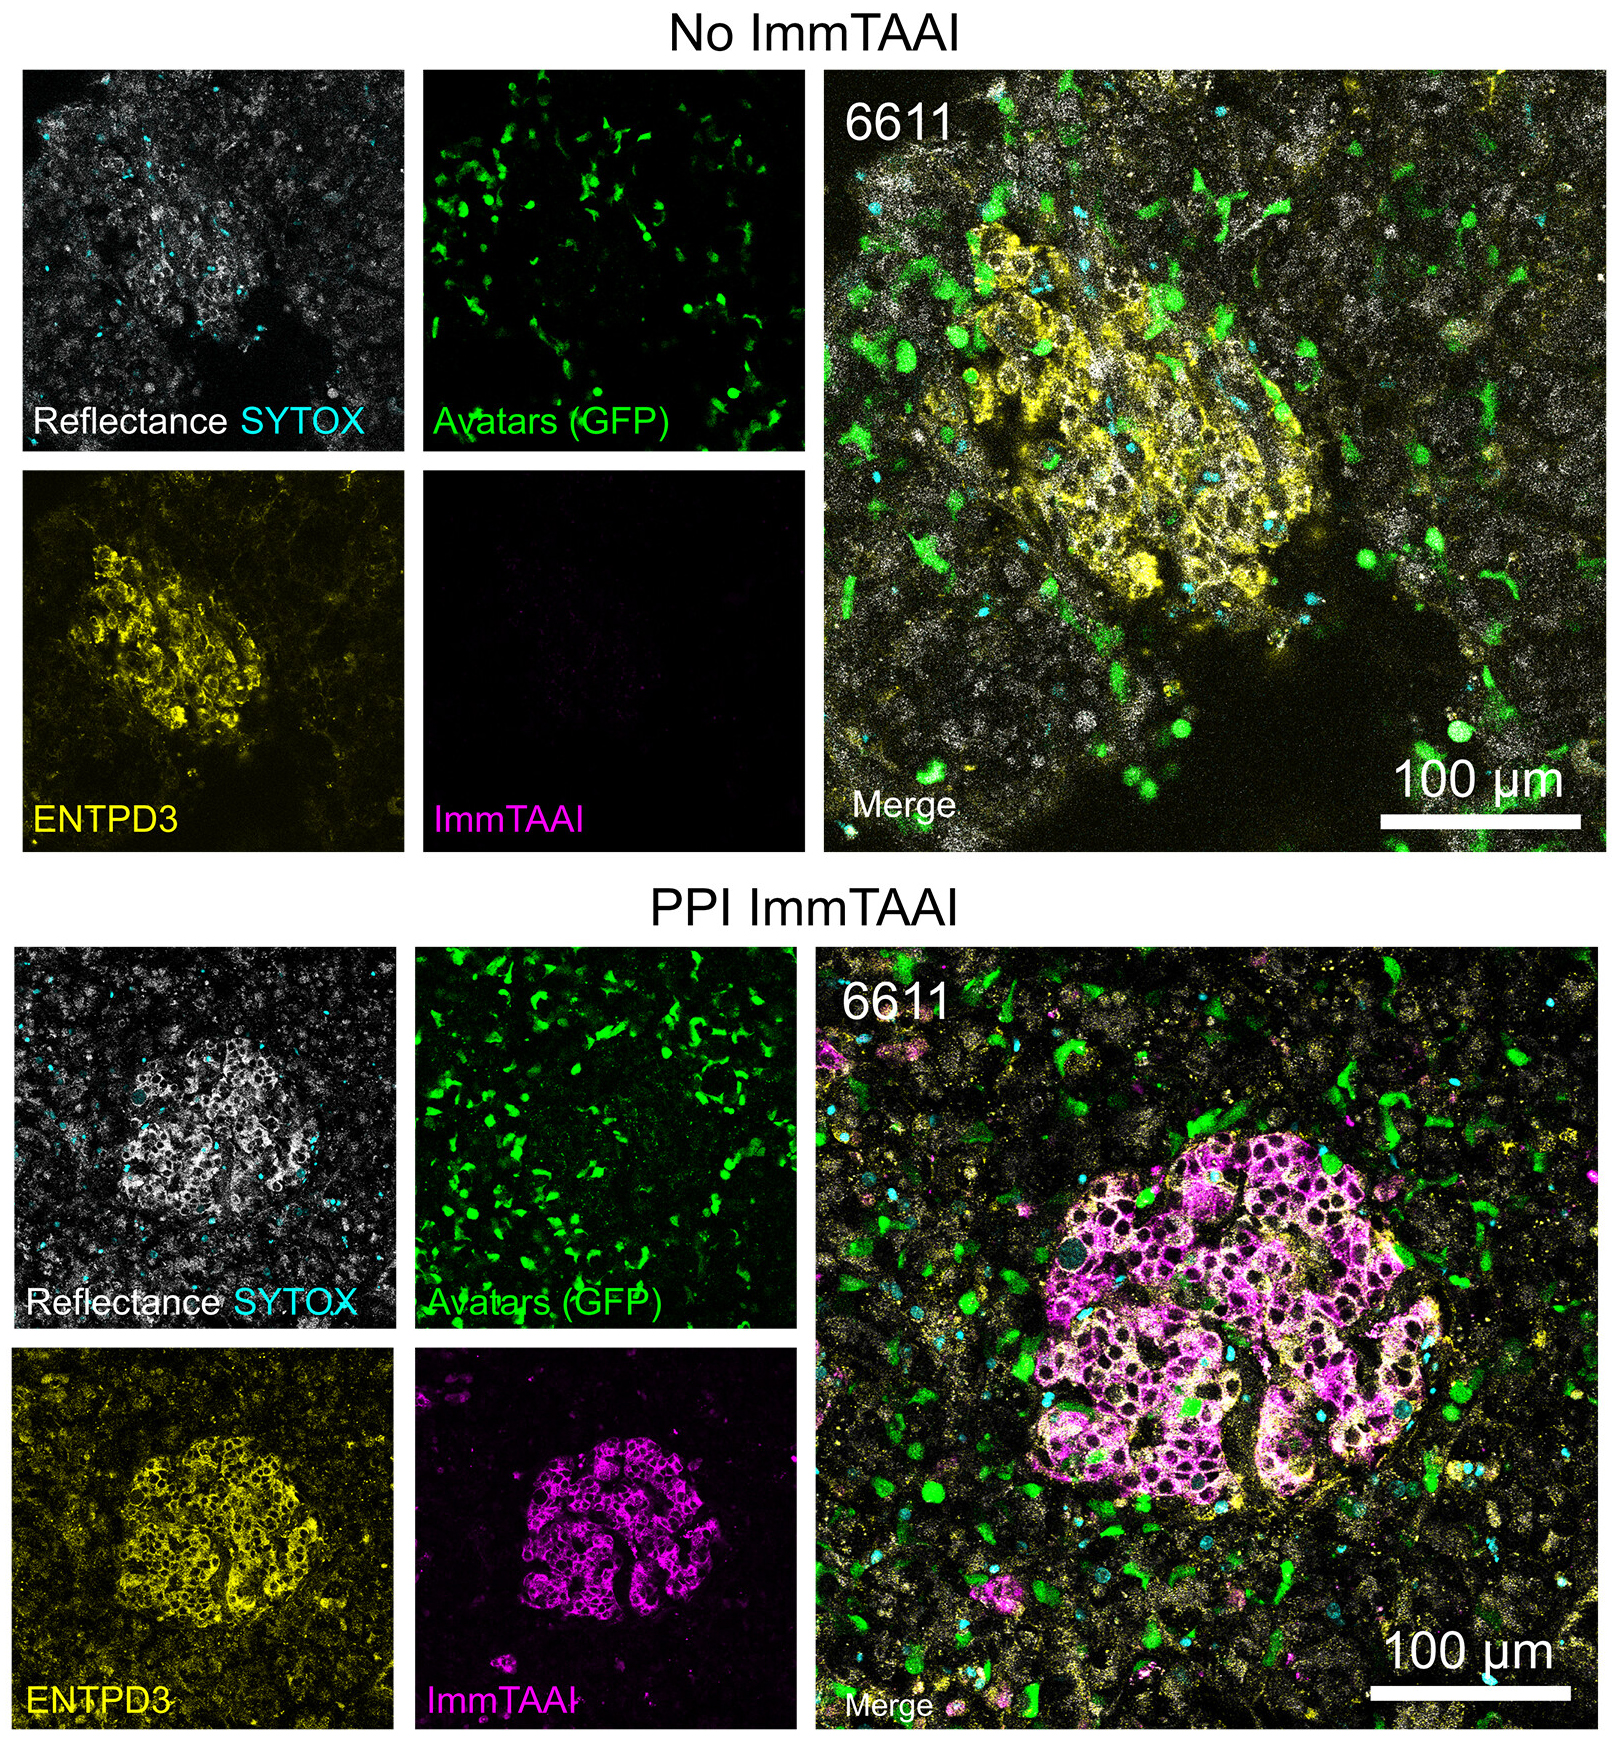

Targeted activation of immune checkpoints is an emerging strategy for treating Type 1 Diabetes (T1D), where autoreactive T cells destroy insulin-producing beta cells. Autoimmune diabetes has been linked to disruption of the PD-1/PD-L1 pathway, which normally suppresses T cell activity to maintain immune tolerance. To address the limitations of systemic immunosuppression, an immune modulating monoclonal TCR against autoimmunity (ImmTAAI) molecule was created to selectively activate PD-1 signaling at the beta cell surface. This is a bispecific molecule that combines a T cell receptor targeting a preproinsulin peptide presented by HLA-A2 with a PD-1 agonist domain, enabling localized suppression of autoreactive T cells.

In a 2026 Science Advances publication, Becker et al. evaluated ImmTAAI function in live human pancreas tissue slices through confocal imaging, binding assays, and functional coculture systems using engineered T cell “avatars” designed to mimic the behavior of autoreactive T cells in T1D. Biotium’s CF®647 succinimidyl ester dye was used to label and visualize ImmTAAI molecules in live and fixed human pancreas slices. This labeling enabled precise tracking of ImmTAAI localization and quantification of its binding to beta cells via confocal microscopy without affecting binding affinity, specificity, or functional potency of ImmTAAI.

The researchers found that ImmTAAI binds specifically and dose-dependently to beta cells in a human leukocyte antigen (HLA)-dependent manner, with increased binding under inflammatory conditions. ImmTAAI treatment increased T cell movement, reduced T cell–beta cell interactions, and suppressed cytotoxic activity of target beta cells. Furthermore, ImmTAAI conferred protection of beta cells from immune attack in cell culture and in tissue slices, and helped preserve insulin secretion in live pancreas slices from a donor recently diagnosed with type 1 diabetes.

CF®647 enabled colocalization studies in a PD/PD-L1 therapeutic model and confirmed selective targeting within complex tissue environments. These findings highlight the value of bright, photostable far-red dyes like CF®647 for imaging-driven validation of targeted immunotherapies.

Live-cell confocal imaging (18 h) of pancreas slices treated with or without PPI ImmTAAI after addition of 200,000 IGRP-specific T cells per slice shows CF®647-labeled ImmTAAI colocalization with ENTPD3. Adapted from Becker et. al. Reproduced under CC BY 4.0.